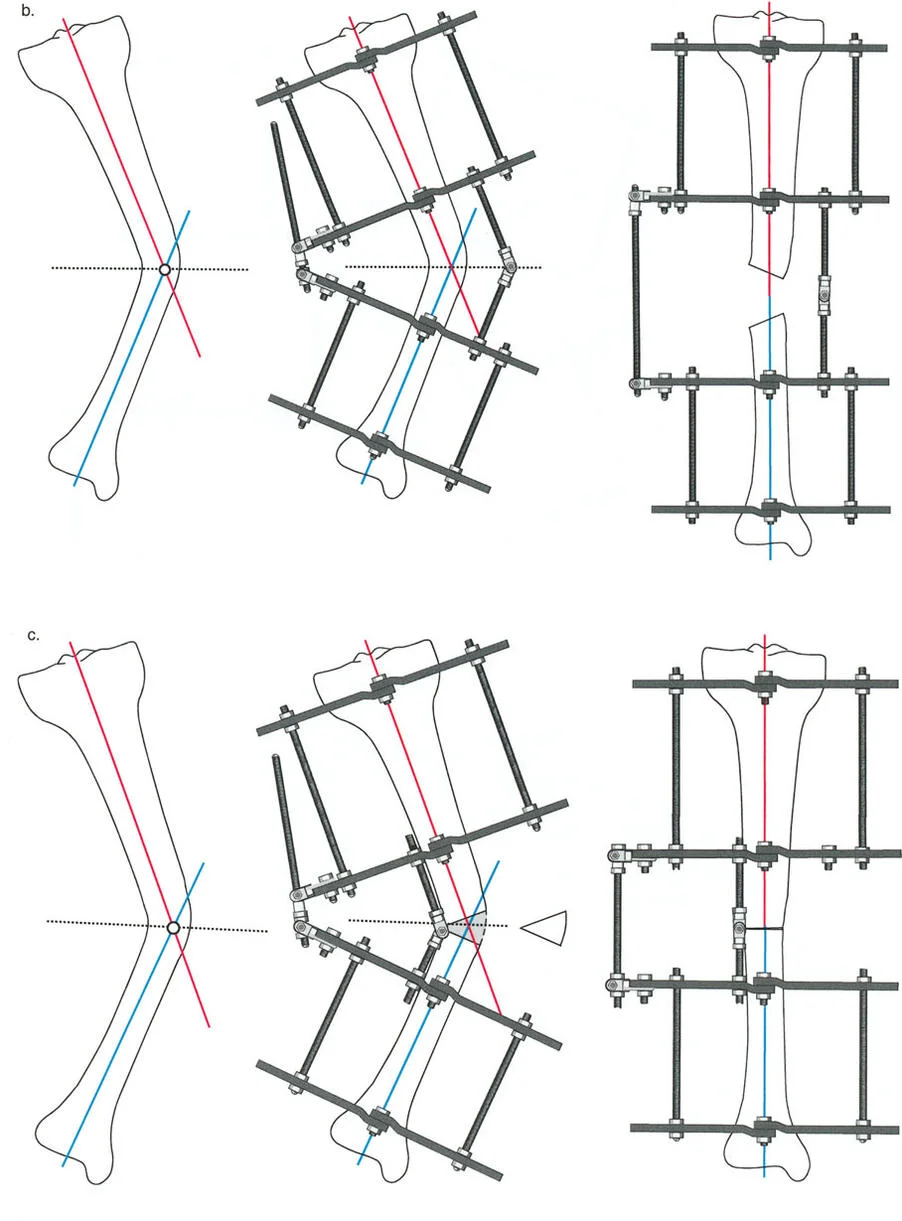

انحراف المحور الميكانيكي (MAD): مقياس الضرر

بناءً على ملاحظات التشريح الطبيعي، تُعتبر مفاصل الطرف السفلي متوازية بشكل طبيعي. أي تشويه لهذه العلاقة يؤثر بشكل متوقع على نقل الأحمال. بينما يمكن لمفصل الورك (كونه مفصلاً كرويًا متطابقًا للغاية) أن يستوعب بعض التغيير في اتجاه الحمل، ومفصل الكاحل محمي بحركة تعويضية معقدة للمفصل تحت الكاحل، فإن الركبة معرضة بشكل استثنائي للتغيرات في المستوى التاجي. إنها مفصل مفصلي يعتمد بشكل كبير على أربطته الجانبية والغضاريف الهلالية لإدارة الأحمال غير المتساوية.

عندما يؤدي تشوه المستوى التاجي إلى اختلال المحاذاة المحورية، فإن محور تحمل الوزن يمر إما وسطيًا أو جانبيًا لمركز الركبة. تُقاس القيمة المطلقة لهذا الانحراف باسم انحراف المحور الميكانيكي (Mechanical Axis Deviation - MAD).

كيفية قياس MAD:

- ارسم المحور الميكانيكي للطرف السفلي (خط مستقيم من مركز رأس الفخذ إلى مركز سطح الساق).

- ارسم قطعة خطية عمودية تمتد من خط المحور الميكانيكي هذا إلى المركز الهندسي الدقيق لمفصل الركبة (نقطة المنتصف بين شوكتي الساق).

- طول هذه القطعة العمودية، المقاس بالملليمترات، هو MAD.

يعكس حجم MAD بشكل مباشر حجم نقل الإجهاد المتغير عبر الركبة. يُعد قياس MAD متفوقًا بشكل كبير على مجرد قياس الزوايا الإجمالية للطرف لأنه يأخذ في الاعتبار التشوهات من أي نوع — بما في ذلك الدوران، الانتقال، والزاوية — ويترجمها إلى قيمة ميكانيكية حيوية واحدة ذات صلة سريريًا.

تأثير مضاعفة القمة (Apex Multiplier Effect)

بشكل حاسم، يأخذ MAD في الاعتبار مستوى (أو ارتفاع) التشوه. يزداد تأثير التشوه الزاوي على المحور الميكانيكي الكلي بشكل كبير كلما اقتربت قمة التشوه من مفصل الركبة. يُعرف هذا باسم تأثير مضاعفة القمة. تشوه زاوي بمقدار 10 درجات في منتصف جسم عظم الفخذ سينتج عنه MAD أصغر بكثير من تشوه بمقدار 10 درجات في الجزء القريب من مفصل الفخذ. لذلك، فإن التشوهات حول المفصل (القريبة من الركبة) تكون أكثر تدميرًا لميكانيكا المفصل وتتطلب تصحيحًا جراحيًا أكثر قوة من تشوهات جسم العظم بنفس الحجم الزاوي.

بعد تحديد محاذاة الطرف السفلي (MAD)، يجب على الجراح تقييم اتجاه المفاصل بشكل منهجي بالنسبة للمحور الميكانيكي. لكل مفصل ميل طبيعي يمكن التنبؤ به بدرجة عالية. تشكل هذه القيم الطبيعية الخطوط والزوايا المرجعية التي تُعد متطلبات أساسية للتخطيط قبل الجراحة ولتحديد مركز دوران الزاوية (CORA).

الهدف النهائي لأي جراحة لتصحيح التشوه هو هدفان:

- استعادة المحاذاة الخطية الطبيعية: القضاء على MAD بحيث يمر المحور الميكانيكي عبر مركز الركبة.

- استعادة اتجاه المفصل الطبيعي: التأكد من أن خط المفصل لكل مفصل يقع بزاوية صحيحة بالنسبة للمحور الميكانيكي، مما يمنع قوى القص التي تدمر الغضروف.